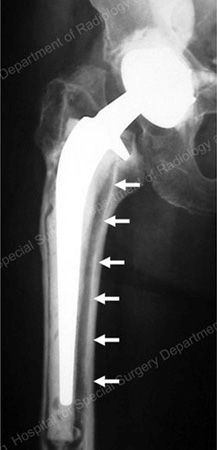

A patient’s immune system will recognize the particles as foreign (not a natural part of the body) and generate an immune response (like an allergic reaction). A strong reaction to the wear particles can result in the destruction of bone around the hip replacement (a condition called osteolysis). If the bone destruction is severe enough, the components of the replaced hip may become loose (Figure 3).

Figure 3: X-ray of a loose total hip replacement prosthesis showing separation of the stem from the bone (as detailed by arrows)

A loose component can move against the surrounding bone, compounding the bone loss. If the bone loss is severe enough, a spontaneous bone fracture can occur (known as a pathologic fracture).